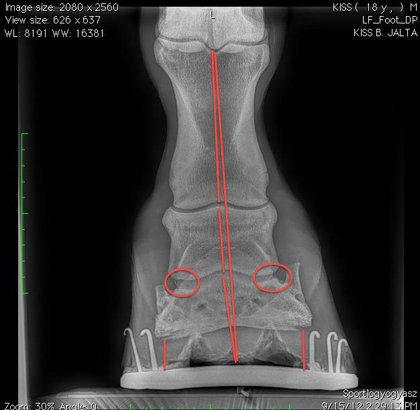

A cél az volt, hogy mellső lábai egyensúlyba kerüljenek. Bal első lába különösen problémás volt az eltolódott mediolaterális egyensúly miatt. A ló lábairól a régi patkókkal, a patkók eltávolítása és a körmölés után, majd az új patkókkal is röntgenfelvételek készültek. Kiváló alkalom volt ez arra, hogy megtapasztaljuk, mennyiben megkönnyíti a kovács és az állatorvos munkáját néhány jó minőségű röntgenfelvétel. Az már csak a hab a tortán, hogy dr. Kis János jóvoltából az ország egyik legmodernebb, érintőképernyős direkt digitális mobil röntgenkészülékét láthattuk munka közben.